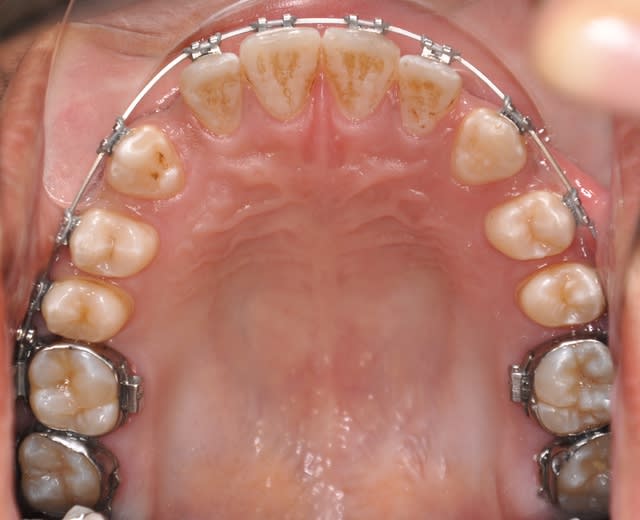

les dernieres photos du cas

- Qu'attends-tu pour fermer les diastèmes en bas ? Il me semble que cela diminuerait la vestibuloversion des incisives supérieures.

- La 4ème photo n'est pas exacte, ton patient à latéroglissé à gauche. Tu l'as prise comme ça volontairement ?

- Tu cherches toujours une solution pour ton problème d'occlusion croisée ?

** oui, j’attends l’alignement et la correction des rotations pour passer à l’acier et ainsi réaliser mon ancrage maximum et le recul des incisives(photos au prochain RDV)

**non, c’est une photo avec miroir qui montre bien les rapport molaires et canines et qui montre le début de la correction de l’articulé en jouant sur le sens transversal de l’arc niti

**oui, je cherche à traiter le coté gauche sans modifier le coté droit